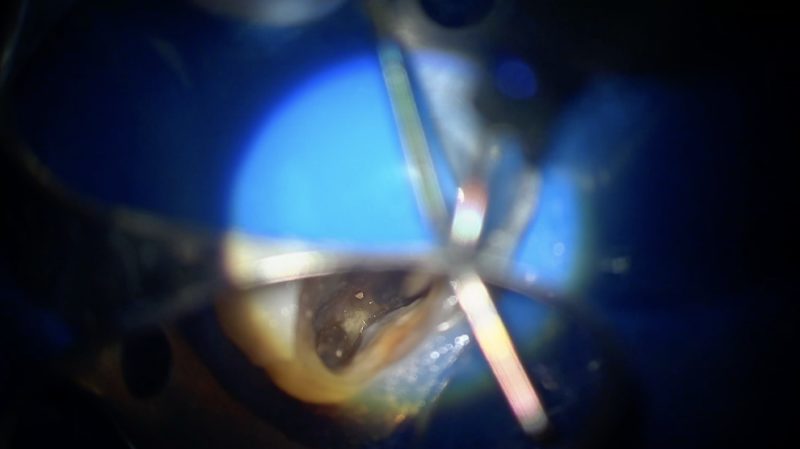

頬側から、舌側からと根管内をきれいにしていたら、簡単に破折ファイルが出てきました。

清掃が進んで根管内が明るく見やすくなってくるとクラックも見つかりました。